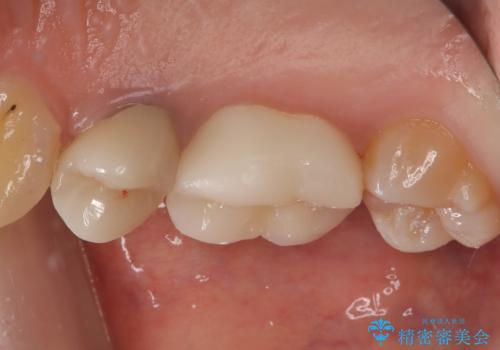

オールセラミッククラウンの膨隆で下部鼓形空隙を適切な大きさに調整しました。

仮歯:11,000円(税込み)

オールセラミッククラウン(スタンダード):121,000円(税込み)